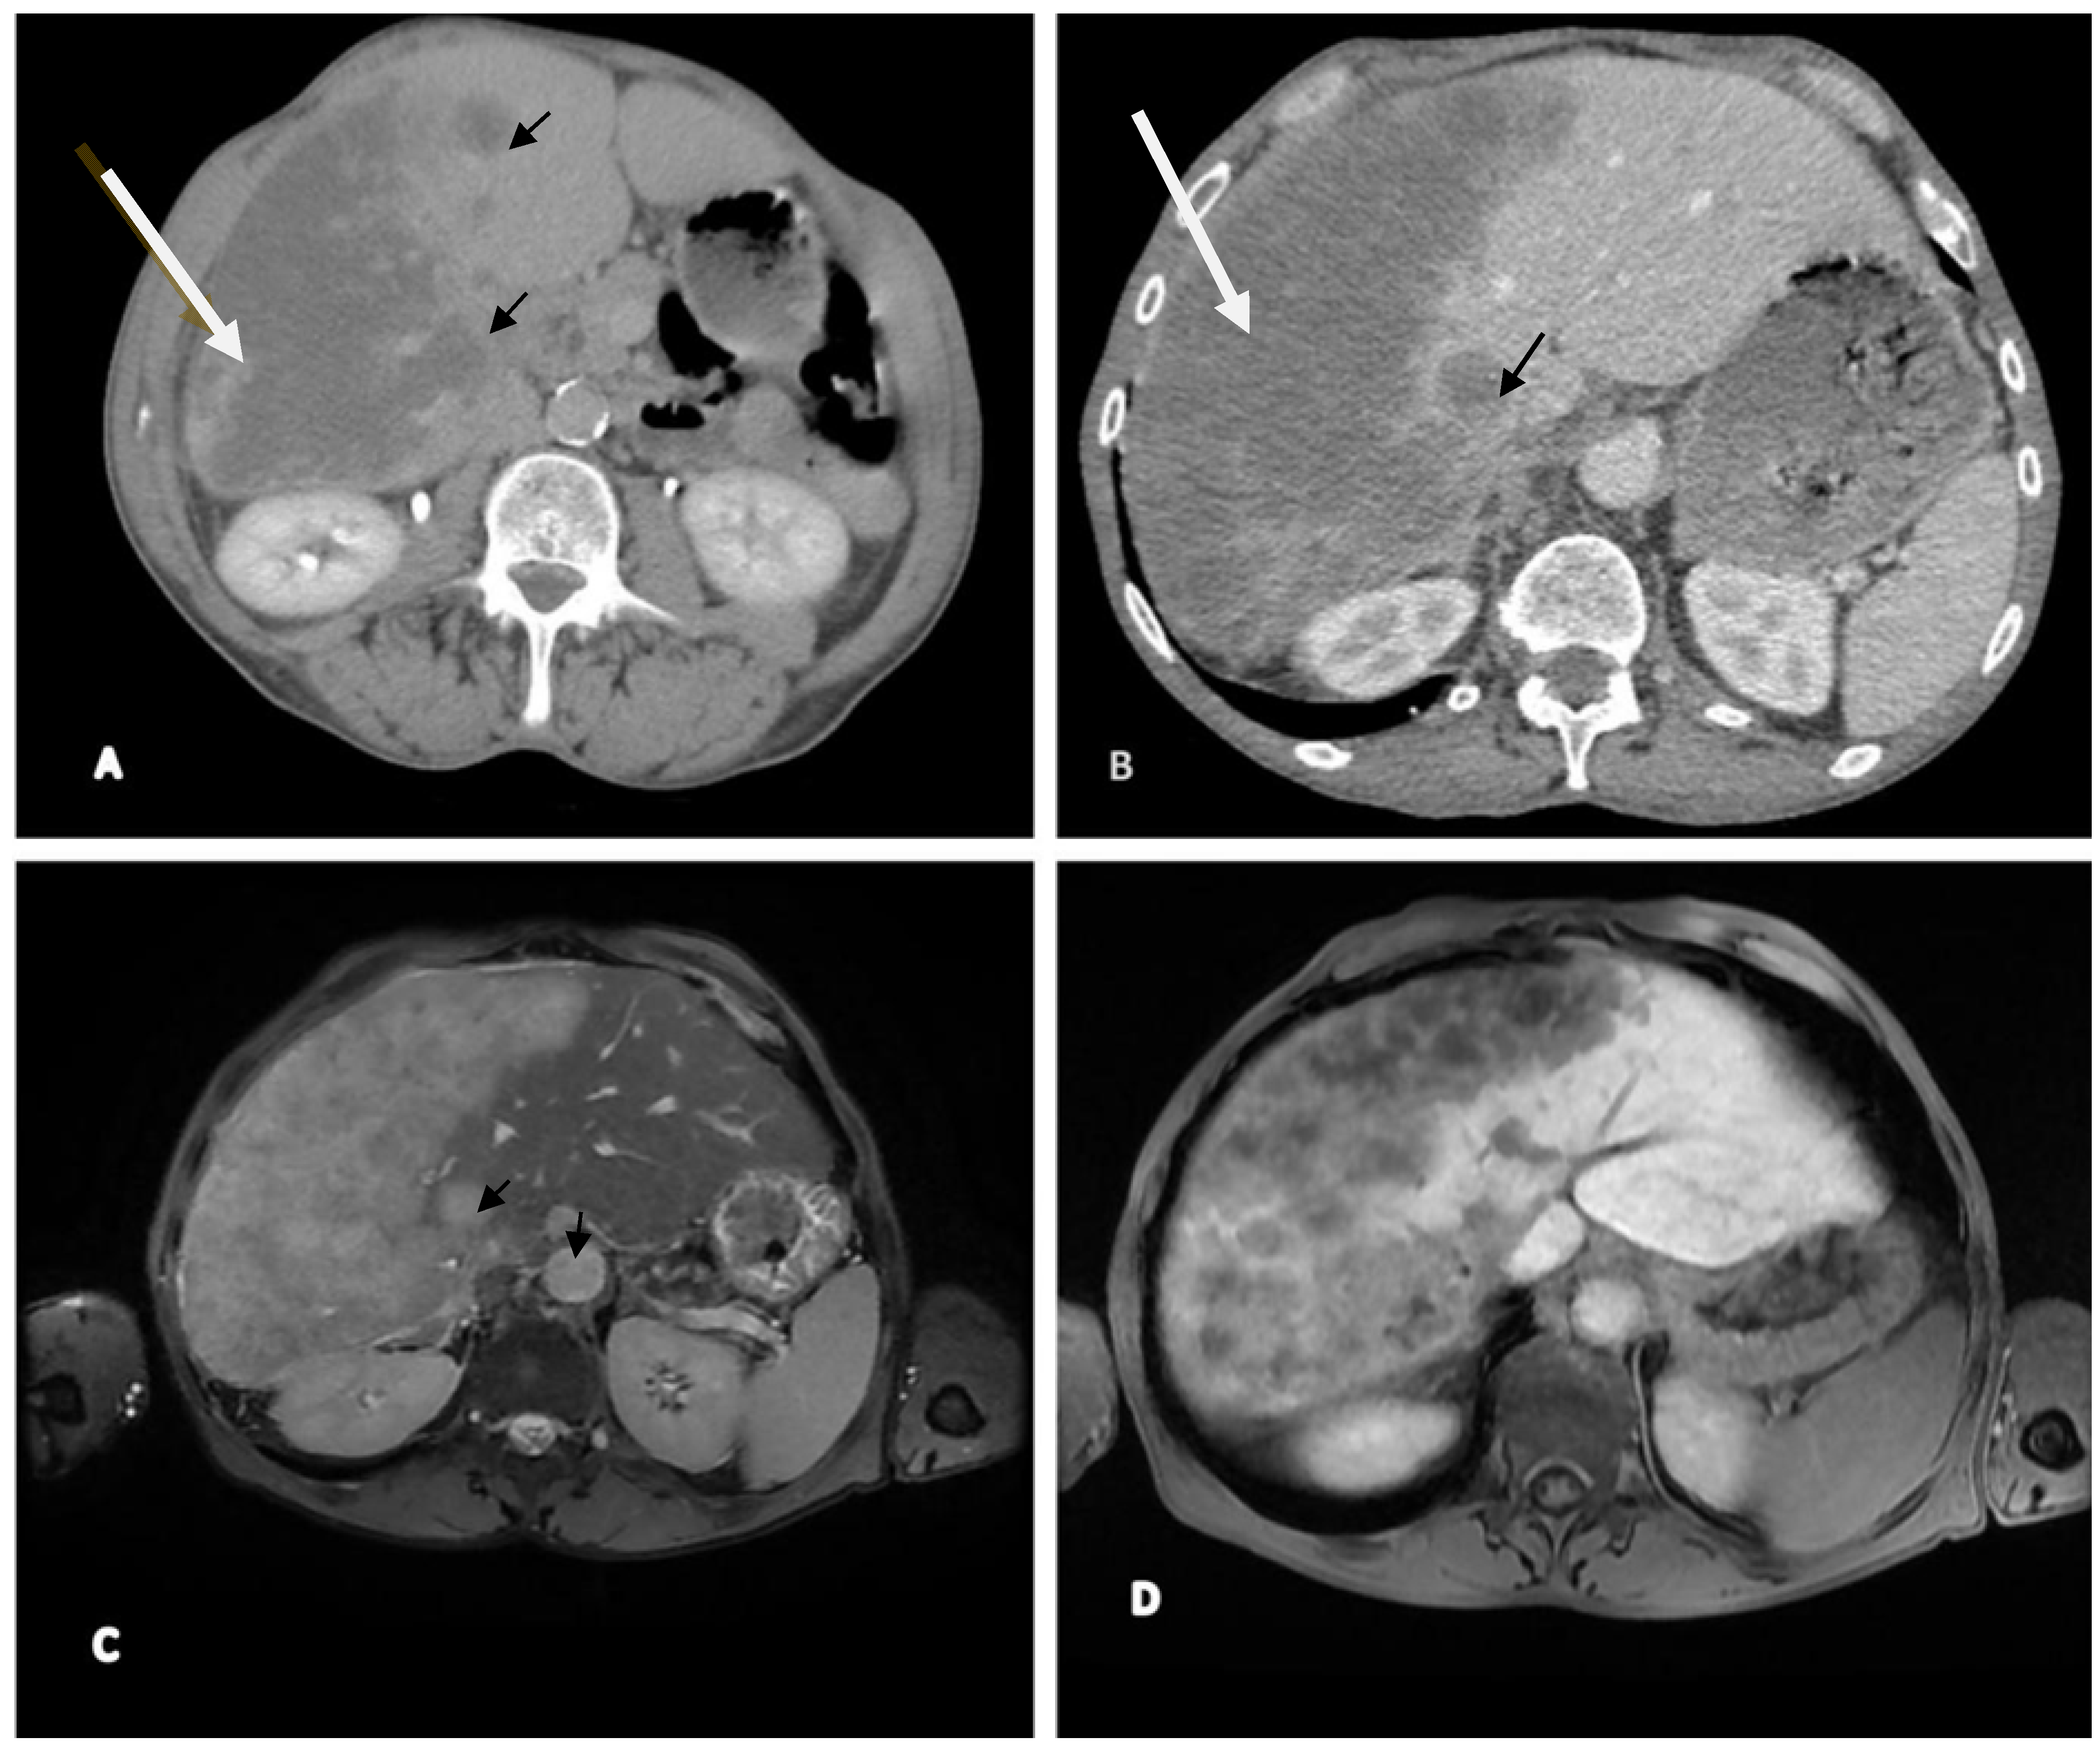

2.2. Imaging (CT and MRI)